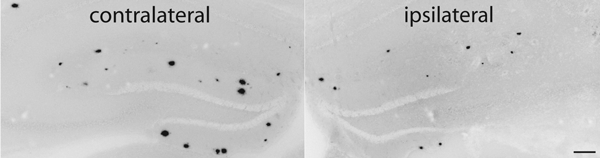

Reduction of amyloid plaque burden (ipsilateral image) following IL-1 overexpression.1

As one of the proinflammatory cytokines shown to be elevated in AD brain, IL-1 was believed to take part in a vicious cycle of pathology and cytokine production by microglia responding to amyloid plaque deposition. To investigate this further, we created a transgenic mouse in which we could induce sustained IL-1 expression in a regionally and temporally specific manner (IL-1XAT). Much to our surprise, when these mice were crossed with a mouse model of Alzheimer’s disease, we found that IL-1 expression led to a reduction in amyloid plaques, rather than the anticipated exacerbation of pathology. Our working hypothesis is that the local inflammation induced by IL-1 enhances phagocytosis, perhaps by infiltrating macrophages, of extracellular amyloid. To explore this hypothesis we are making use of mice lacking chemokine receptors required for macrophage recruitment as well as chimeric mice harboring bone marrow.